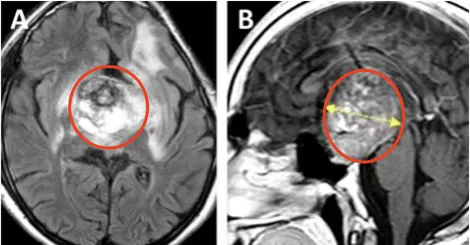

术前情况:MRI显示鞍区与丘脑存在巨大肿瘤,归类为Bcentral病变的复发性毛细胞星形细胞瘤,侵犯左侧海马旁回及侧脑室上部。肿瘤体积68.1 mm³,深度44.4 mm,侧面角21.9°。

术后情况:术后MRI显示肿瘤近全切,双侧大脑前动脉A2段灌注正常,视交叉、视神经束、垂体柄及下丘脑结构保全。